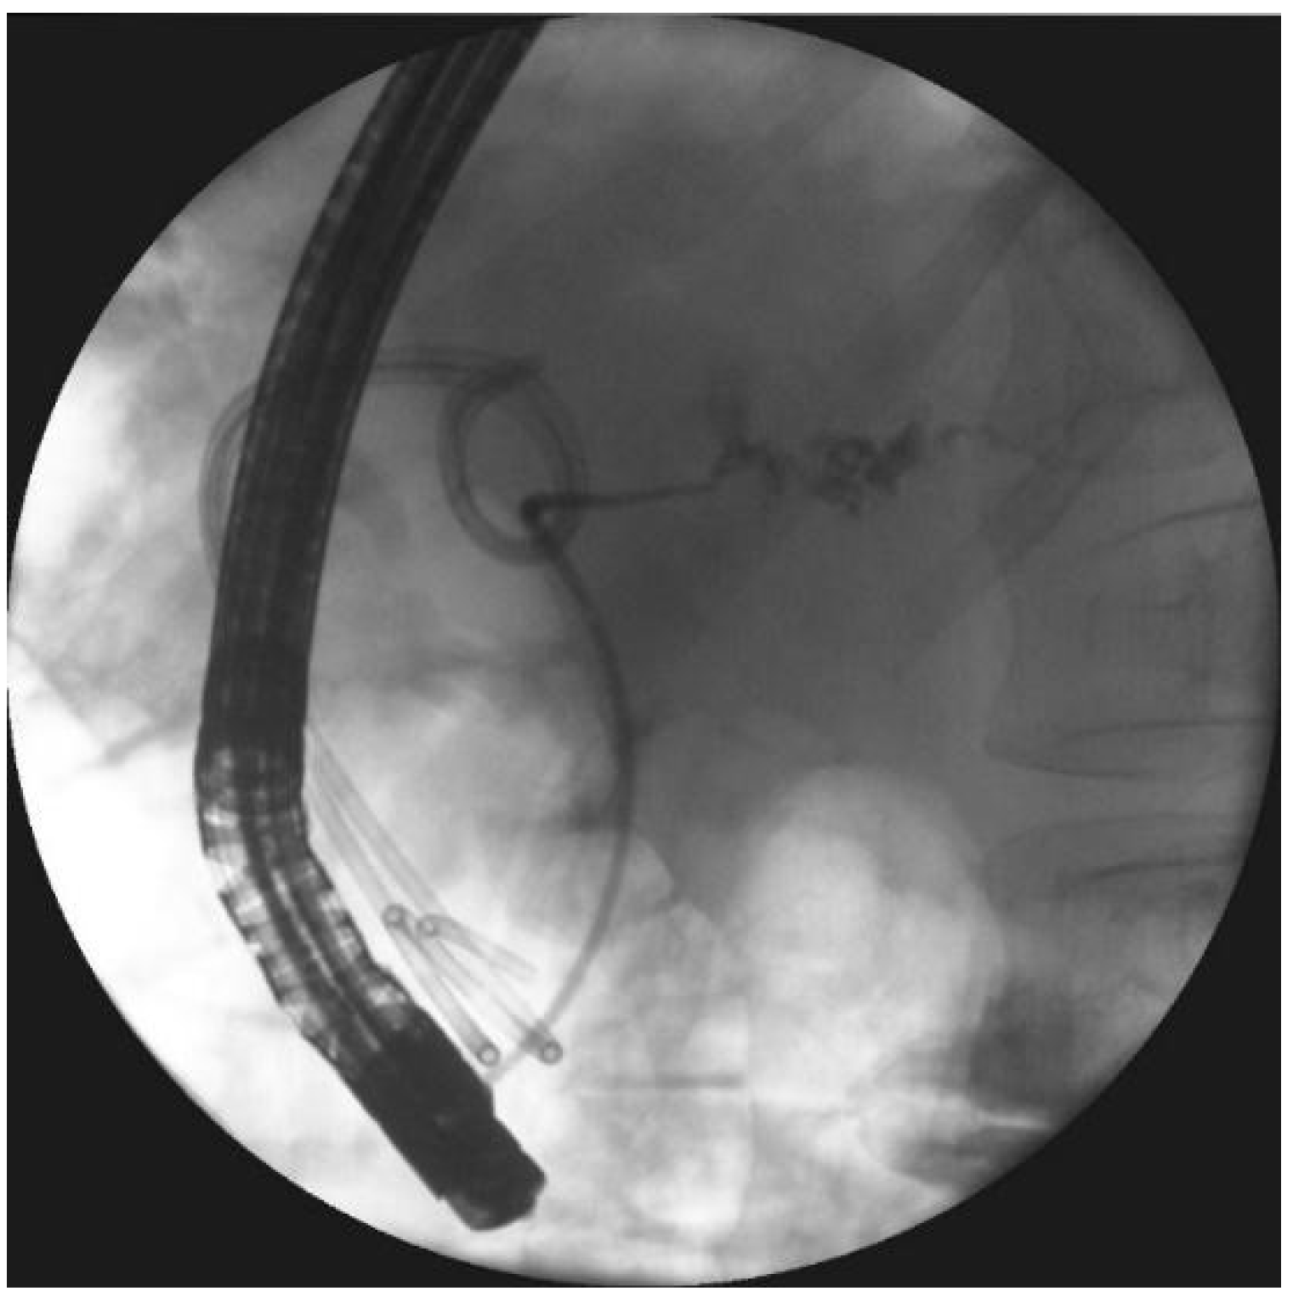

- Smoczyński, M.; Jagielski, M.; Jabłońska, A.; Adrych, K. Endoscopic necrosectomy under fluoroscopic guidance- a single center experience. Wideochir. Inne. Tech. Maloinwazyjne. 2015, 10, 237–243. [Google Scholar] [CrossRef] [PubMed]

- Smoczyński, M.; Jagielski, M.; Siepsiak, M.; Adrych, K. Endoscopic necrosectomy through the major duodenal papilla under fluoroscopy imaging. Arch. Med. Sci. 2018, 14, 470–474. [Google Scholar] [CrossRef] [PubMed]

| Endoscopic necrosectomy under fluoroscopic guidance (endoscopic debridement) | Procedure that enable to remove necrotic tissues from necrotic cavity through transmural fistula under fluoroscopy with use of various types of endoscopic tools. Indication for endoscopic debridement is WOPN containing poorly-liquefied necrotic tissues. |